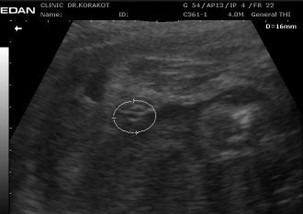

ทีมคุณแม่ ธันวาคม กำหนดแตกวันไหน น้องเพศอะไรกันบ้าง มาแบ่งปันกันชมค่ะ 31+1 สัปดาห์ #หมอบอกที่ทำวงกลมไว้ให้เป็นเพศน้องคะ แต่หมอไม่บอกนะคะว่าเพศไหน ให้ลุ้นเอา🤣 #ท้องแรกคะ นี่จู๋น้องมั้ยคะ?